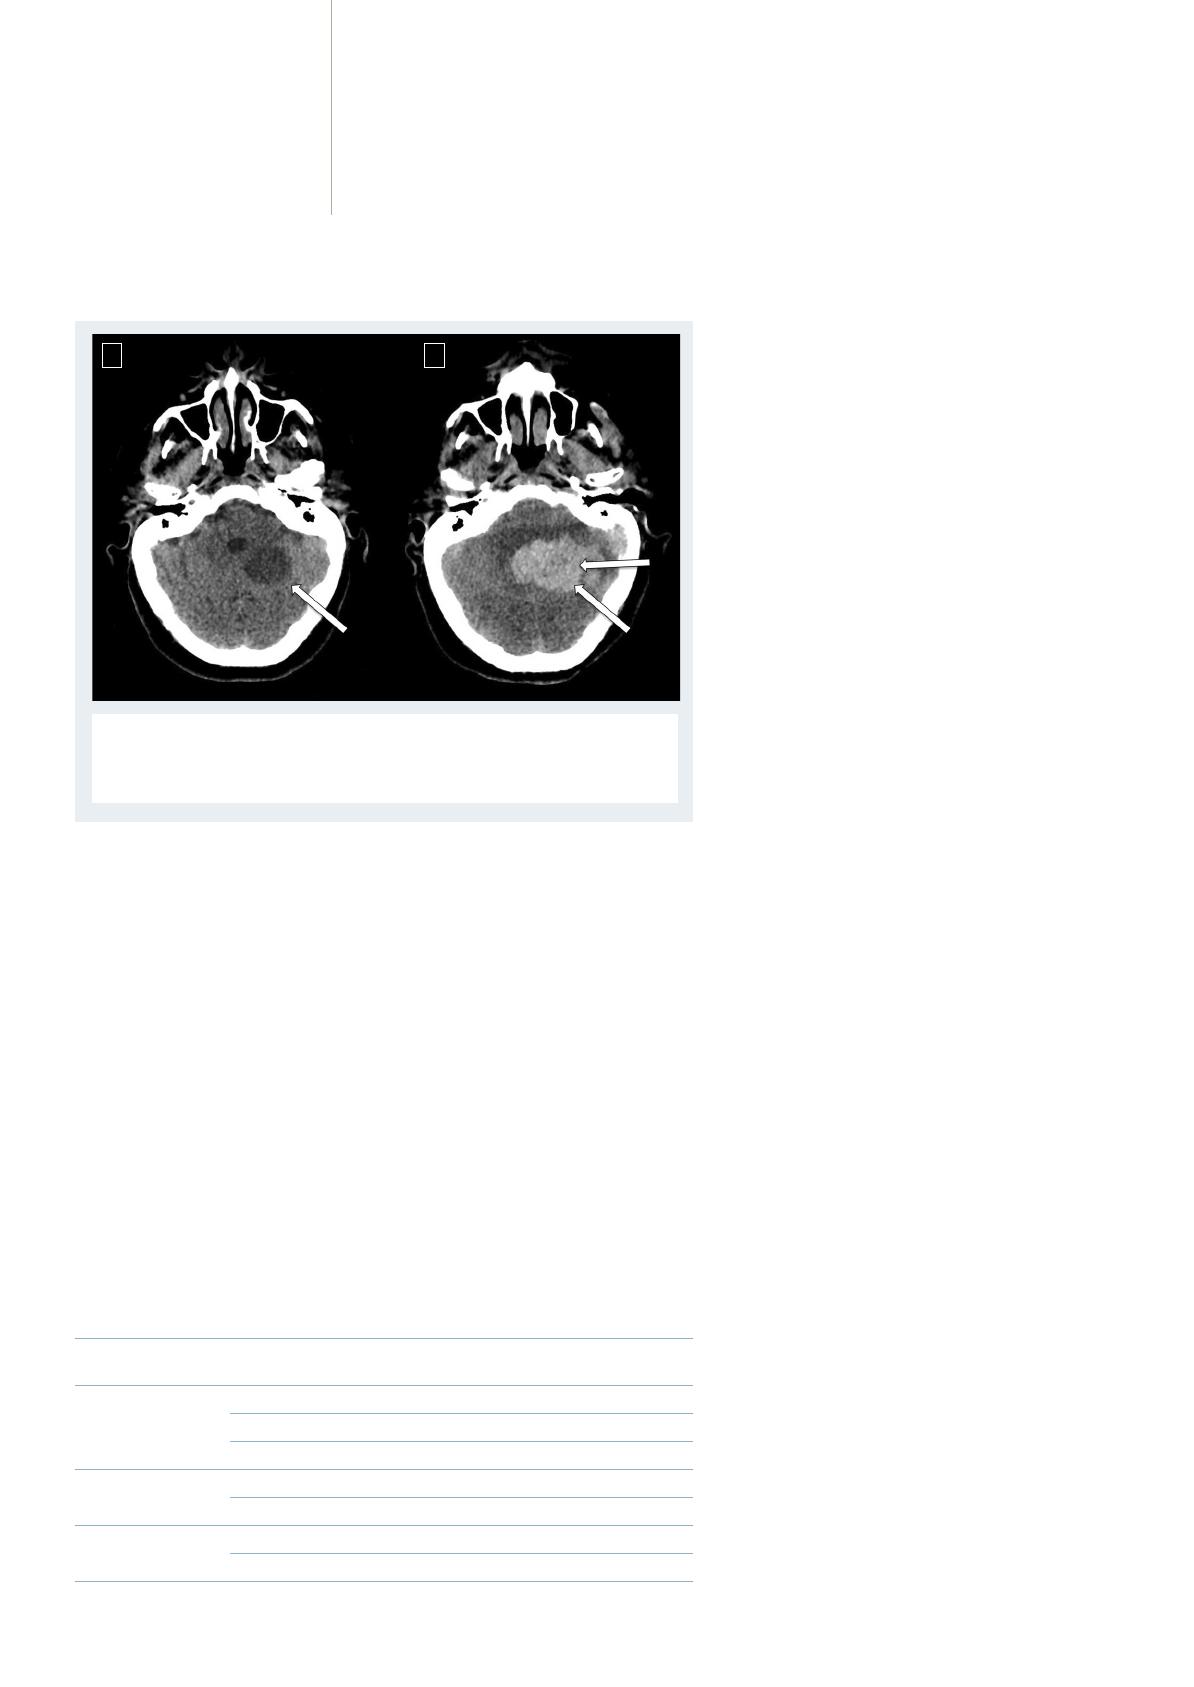

L’indication d’une anticoagulation efficace – c’est-

à-dire curative – par héparine non fractionnée ou

héparine de bas poids moléculaire en phase aiguë de

l’IC reste exceptionnelle à cause du risque de trans-

formation hémorragique cérébrale (ou plus rarement

d’hémorragie systémique) lié à ce traitement. Toutes

les études à l’heure actuelle ne montrent aucun

bénéfice du traitement anticoagulant en phase aiguë

de l’IC. Le bénéfice de ce traitement, en particulier

chez les patients qui présentent une FA, reste contre-

balancé par l’augmentation du risque d’hémorragies

intracérébrales symptomatiques (figure 2).

À ce jour, l’étude HAEST (the Heparin in Acute

Embolic Stroke Trial) est la seule étude réalisée à la

phase aiguë de l’IC chez les patients en FA (7). Elle

montre que l’héparine (de bas poids moléculaire

dans cette étude) augmente le risque hémorragique

et que ce traitement n’apporte aucun bénéfice par

rapport à l’aspirine à la posologie de 160 mg par jour.